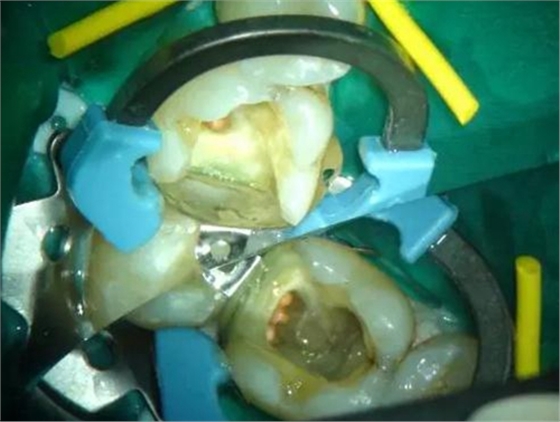

圖1 磨牙根管治療后進(jìn)行核修復(fù)。Palodent V3節(jié)段型成型片、分牙器及楔子均已就位。成型片不會受到橡皮障的影響。可以看到遠(yuǎn)中洞型底部成型片的良好貼合。窩洞已酸蝕及涂布粘接劑,牙面呈“潮濕”狀態(tài)。使用橡皮障更利于術(shù)區(qū)濕度控制。然后向窩洞注射SDR。要注意避免:粘接劑在根管口堆積。SDR注射針頭可以探入根管口。雖然SDR的固化深度是4mm,但是建議現(xiàn)在根管口及髓底涂布薄層SDR并固化。此處位置太深,光固化燈可能光強(qiáng)不夠。然后再疊加SDR,直至低于洞緣2-3mm。